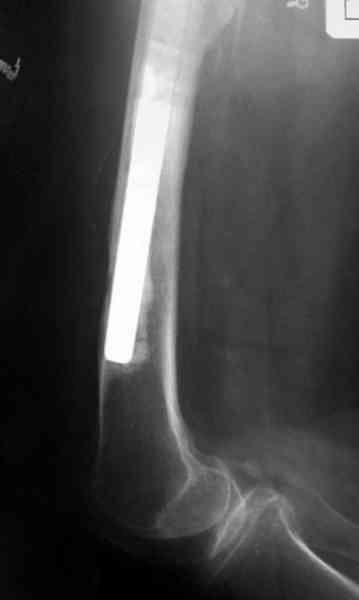

Приглашенный хирург установил ревизионный вариант бедренного компонента без замены ацетабулярного компонента, что осложнилось нагноением и свищами на уровне сустава и средней трети бедра. После двухгодичного безуспешного лечения перевязками и антибиотиками больная обратилась к нам на консультацию.

Для спейсера в бедро использовал старый длинный бедренний компонент меньшего диаметра, облепленный со всех сторон цементом с антибиотиком.

№3-6 снимки с осложнением

и последние снимки.